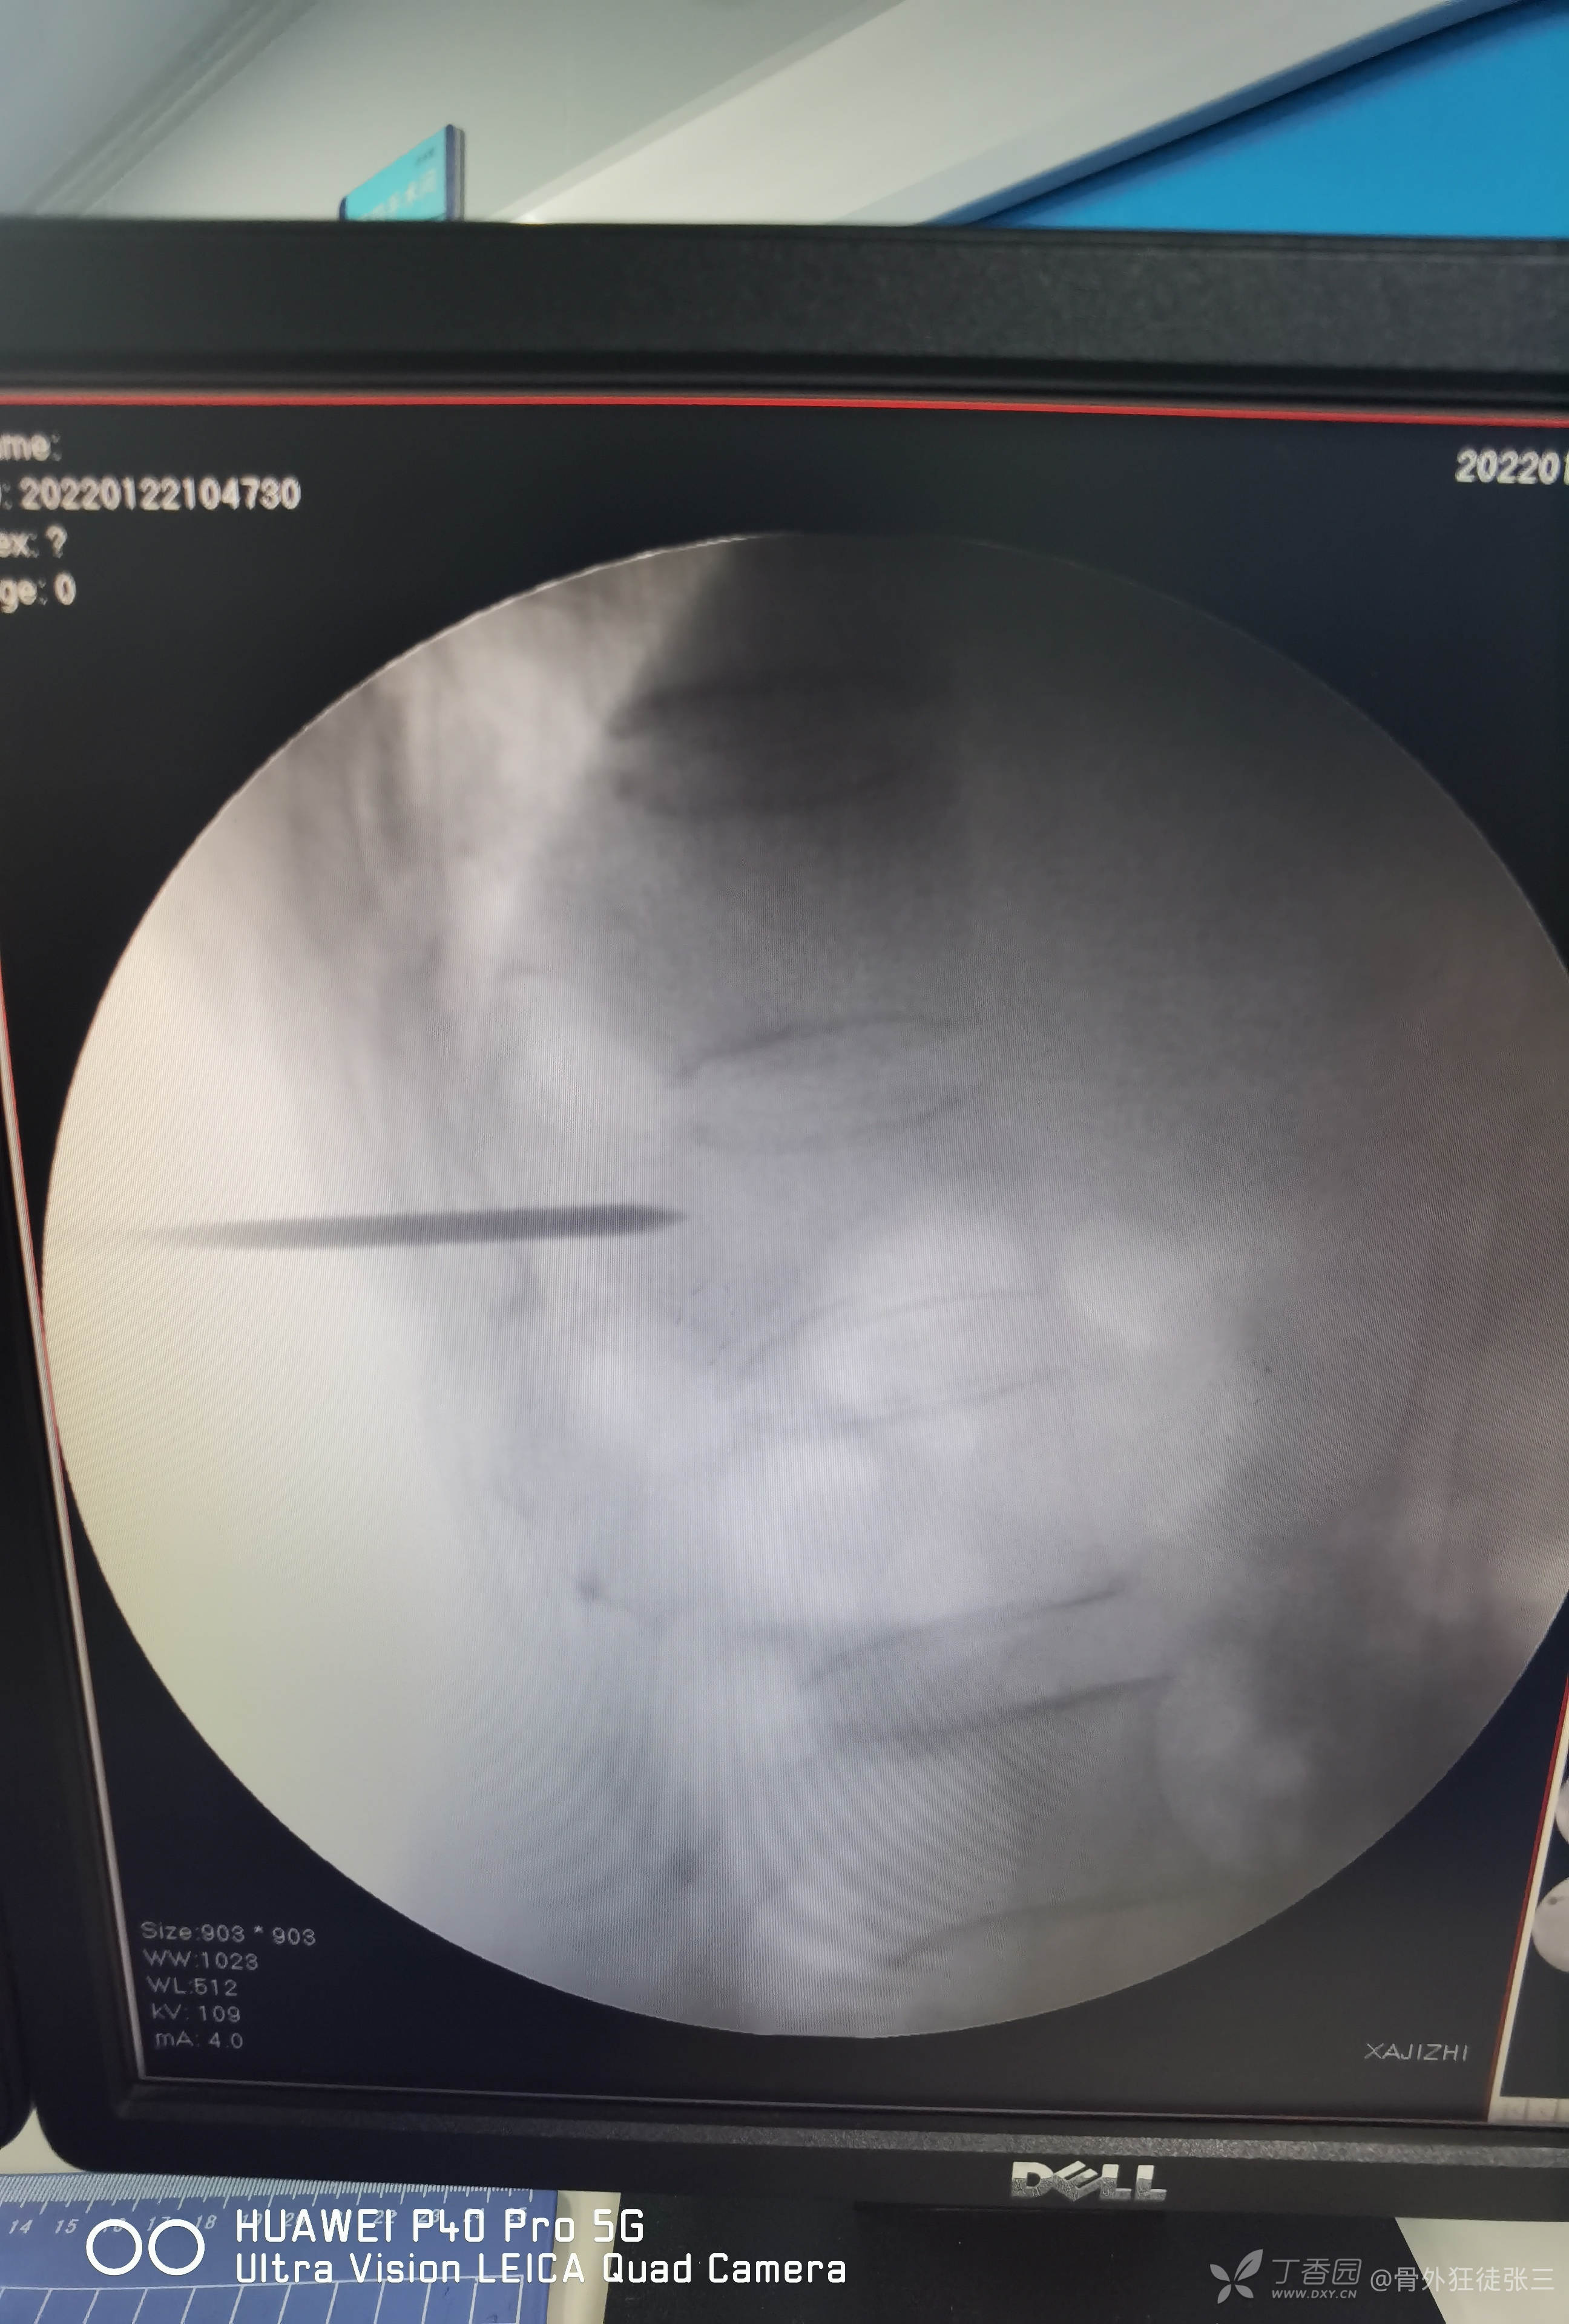

术前讨论后行经皮穿刺椎体成形术。

术前定位

一共注入4ml骨水泥

单侧穿刺,